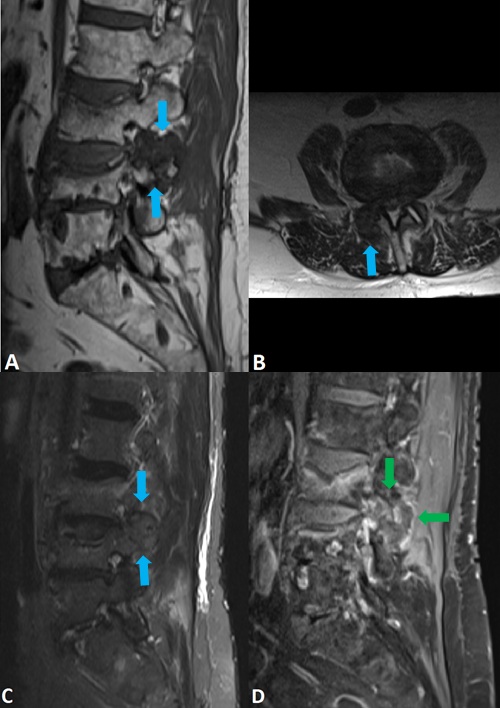

A ressonância magnética revelou a presença de edema medular ósseo no interior destas vértebras, confirmando evolução recente destas fracturas. Adicionalmente, mostra lesão com cerca de 3,5 cm de maior eixo a envolver ao maciço articular posterior direito de L3-L4 (figura 2). A lesão é discretamente lobulada, bem definida, e apresenta-se predominantemente hipointensa nas ponderações T1 e T2 (A e B em figura 2), com realce periférico e reforço de sinal no estudo dinâmico (D em figura 2).

Figura 2: Imagens de ressonância magnética da coluna lombar (Siemens Magneton SymphonyTM, (A) T1 sagital, (B) T2 axial, (C) T2fs sagital, (D) T1fs axial, após administração endovenosa de gadolínio ) revela lesão lobulada adjacente às facetas articulares L3-L4 direitas (seta azuis). A lesão é marcadamente hipointensa em T1 (A), com sinal predominantemente hipointenso em T2 (B e C) e com realce periférico no estudo dinâmico (seta verde em D).